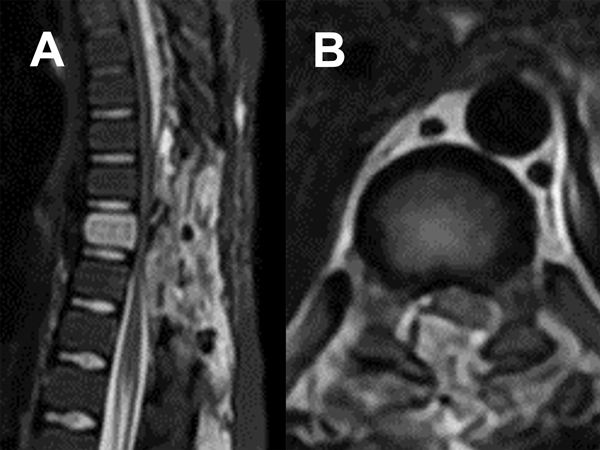

Durante el procedimiento se realizó laminectomía D8 y D9 con exéresis del componente epidural. Durante la cirugía, la lesión fue muy hemorrágica, lo que dificultó la hemostasia. La evolución inicial fue favorable con recuperación progresiva del déficit neurológico. En el cuarto día postoperatorio presentó nuevo deterioro motor. La RM (Figura 3) mostró un hematoma compresivo en el lecho quirúrgico. Se indicó nueva cirugía de evacuación. El paciente logró mejoría continua y progresiva de su déficit.

Figura 3. RM postquirúrgica inmediata. A) Secuencia T2 sagital. B) Secuencia T2 axial.